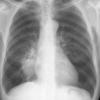

Case 2 Lingular pneum PA

Date: 04/17/2005

Views: 6418